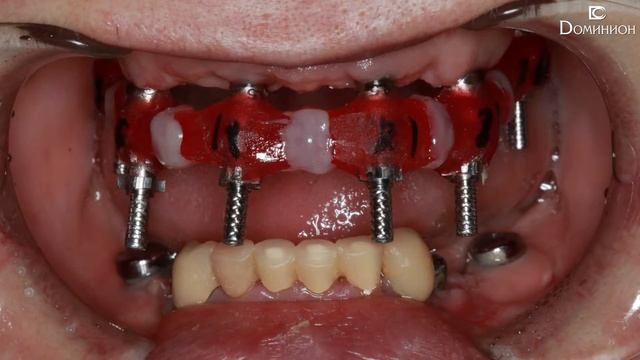

Имплантация и установка металлокерамических коронок. Левковский В.А. (Клиника Доминион) смотреть онлайн

00:48

Имплантация и установка металлокерамических коронок. Левковский В.А. (Клиника Доминион)

Уход и лечение: медицинские процедуры 382 просмотров